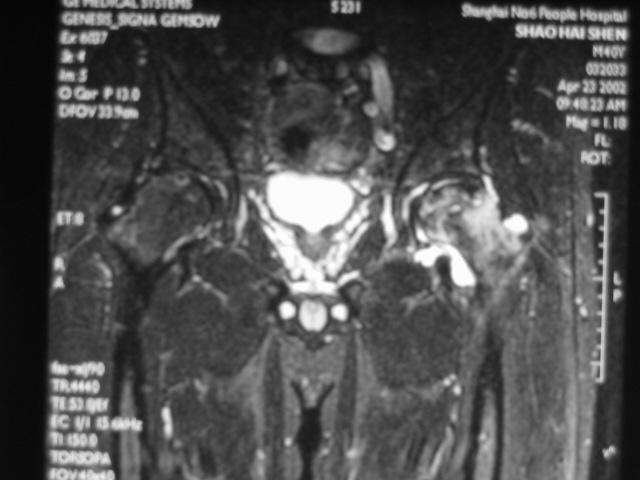

MRI诊断

MRI扫描技术

患者取仰卧位,扫描范围自髋臼上3cm至股骨粗隆下。

层厚5mm,层间距1mm连续扫描。

选择自旋回波SE序列T1WI、T2WI及STIR冠状面扫描,横轴位T1W扫描。

0期

患者无自觉症状,X线、CT、核素扫描及MRI等检查均为阴性。

但骨缺血坏死改变已存在,已有髓腔压力增高,骨髓活检可证实骨缺血坏死存在。

此期被称为股骨头缺血坏死临床前期,也称安静髋。

Ⅰ期

髋关节间隙正常,股骨头光整、不变形。

典型的MRI表现为股骨头前上部负重区在T1W上显示线样低信号区,T2W上显示为局限性信号升高或“双线征”。

在MRI上出现“双线征”,这是股骨头缺血坏死的特异性MRI表现之一。

Ⅱ期

在T1W上,股骨头前上部负重区,有硬化缘围绕较低、不均匀信号的新月形坏死区。

在T2W上,病灶为星月形高信号区。

在X线平片上,股骨头负重区内可见高密度的硬化区,内可伴有小囊样改变。

Ⅲ期

髋关节间隙正常,无狭窄。

股骨头表面毛糙、开始变形。

软骨下皮质出现骨折,进一步发展出现轻微塌陷、阶梯状改变。

新月体形成:新月体代表无法修复的坏死骨发生引力性骨折,在T1W上为带状低信号区,T2W上,由于细胞内液渗出或关节液充填骨折线而呈高信号

股骨头表面软骨的完整性受到一定影响。